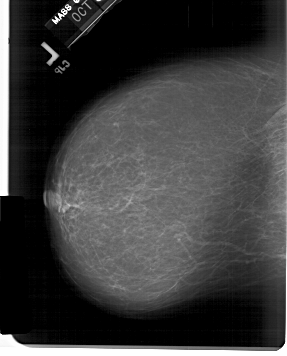

A_1583_1.LEFT_MLO

A_1583_1.LEFT_CC

LEFT_CC LINES 6046 PIXELS_PER_LINE 4876 BITS_PER_PIXEL 12 RESOLUTION 43.5 NON_OVERLAY

LEFT_MLO LINES 6796 PIXELS_PER_LINE 4996 BITS_PER_PIXEL 12 RESOLUTION 43.5 NON_OVERLAY